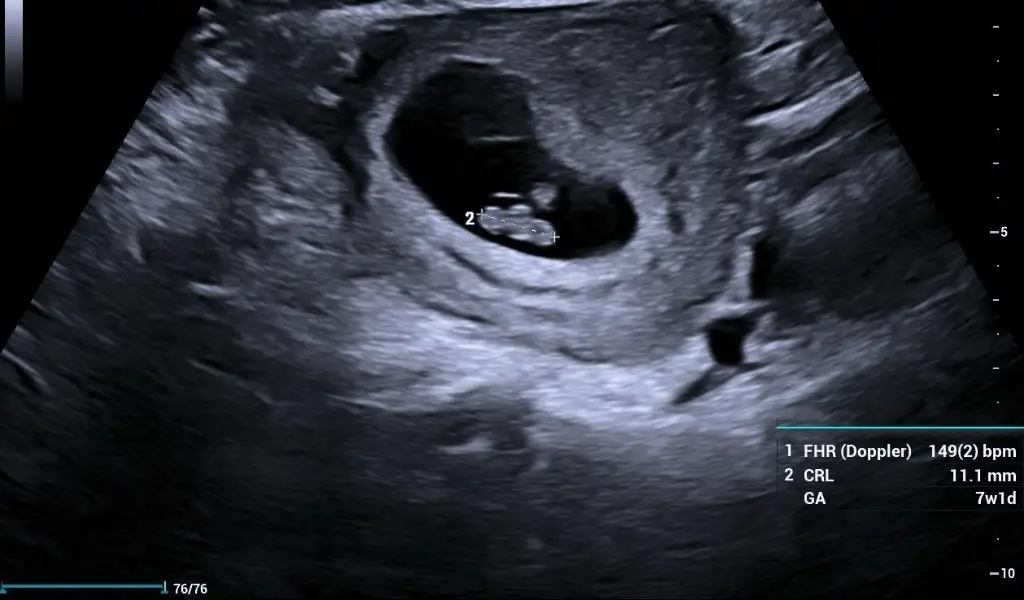

Kızlar benimkinide tahmin edin yaa kese yuvarlakmı ovalmi ben anlamıyorum burda 6+4 😂😂